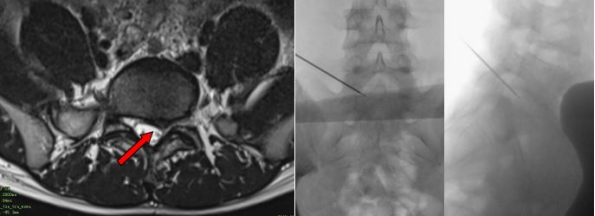

16岁的体校生小李,反复腰痛伴左下肢麻痛5月余,经系统保守治疗无效,入院前1周左下肢麻痛明显加重,无法正常上学。腰椎MR显示腰5/骶1椎间盘向左后突出,骶1神经根被卡压。考虑到患者是一名16岁的体校学生,如果采用常规的开放手术融合内固定治疗,则意味着患者体校生涯的结束,如果采用常规的孔镜辅助下微创摘除椎间盘,因为术中要切断纤维环,术后需要长时间的休息,将严重影响学业,也容易复发。根据病情及个人愿望,利用斜面入针法克服了高髂嵴及骨盆骨骺线未闭合等不利因素,精准施治,对患者实施了腰5/骶1椎间盘低温等离子髓核消融成形术。手术只需局麻,术中患者全程清醒,与医生交流自如,术后症状消失,穿刺口极微小,患者对治疗效果十分满意。

术前腰椎MRI显示椎间盘突出明显,侧隐窝狭窄 术中精准定位